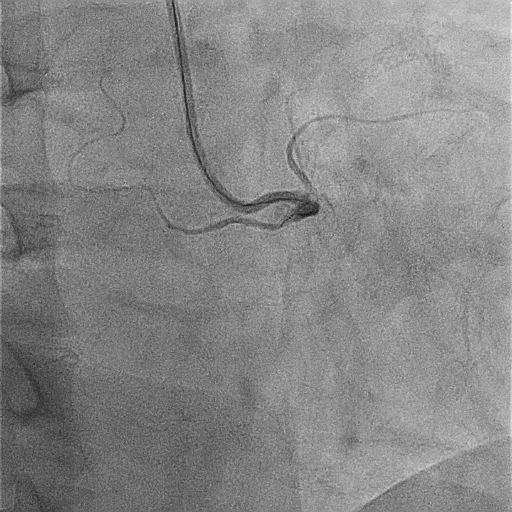

A 51-year-old man presented with stable angina and previously failed right coronary artery (RCA) CTO PCI. During RCA CTO PCI (Figure 1), the wire was inserted into the extraplaque space (Figure 2, Video 1). Intravascular ultrasound (IVUS) showed a hematoma (Figure 3A, Video 2). Live 3-dimensional tip detection IVUS wiring was successful (Figure 4, Video 3). A FineCross microcatheter (Terumo) was placed over the first wire into the extraplaque space and blood was withdrawn by connecting a negative indeflator to the microcatheter. Stents were deployed (Figure 5) and postdilated. Post-IVUS showed almost complete resolution of the hematoma (Figure 3B, C; Video 4) with good results (Figure 6, Video 5).